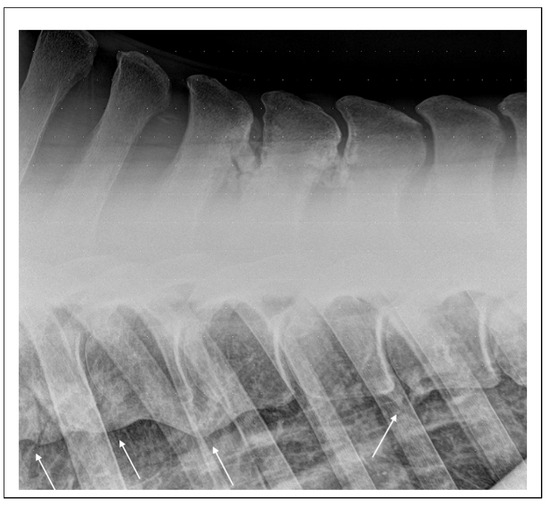

5.2. Diagnostic Imaging Findings